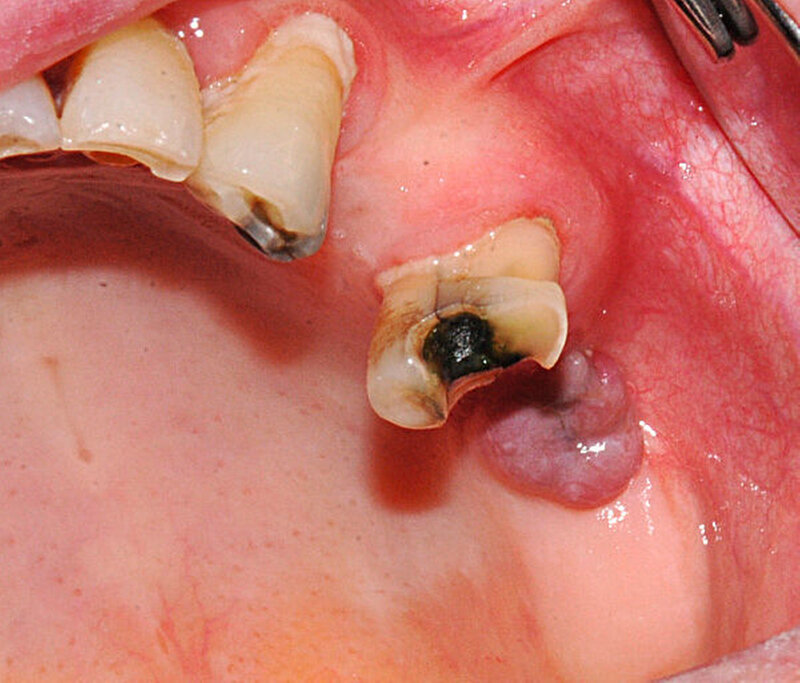

Klinisch wird für enoral gelegene braune Tumore beschrieben, dass sich diese als schmerzhafte, harte und klar palpable Schwellungen darstellen [Triantafillidou, Zouloumis et al., 2006], meist steht jedoch die Symptomatik des Hyperparathyreoidismus im Vordergrund.